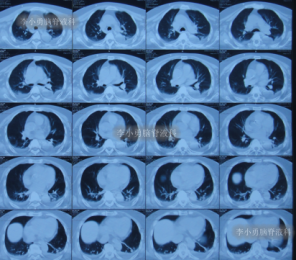

在李小勇主任的引领和培养下,一支技术过硬、敢于担当的医疗团队迅速成长。王光主任作为团队的核心骨干,深得李小勇主任技术精髓,在脑脊液引流、感染控制和围手术期管理方面经验丰富。他介绍,此次救治的71岁女性患者,情况就非常典型且危重。该患者因脑出血、动脉瘤术后继发脑积水,在外院接受了脑室腹腔分流术后,不仅症状未缓解,反而迅速恶化,出现持续昏迷、高热,复查发现脑积水进行性加重,生命垂危。经病友推荐,家属带着最后一线希望,于2021年9月将患者送至北京医大中西医结合医院脑脊液科。“患者来时意识不清,肺部有严重感染,右侧肢体偏瘫,脑积水的‘闸门’——分流管,很可能已经失效甚至成为感染源。”王光主任回忆道。面对这个“烂摊子”,科室迅速启动疑难病例讨论。在李小勇主任的总体指导下,以王光主任为主力的治疗组,为患者制定了周密的“三步走”方案。

引流是基础,但战胜感染、改善患者全身状况才是康复的关键。在持续引流的同时,团队根据药敏结果使用敏感抗生素,并辅以营养神经、维持水电解质平衡、强化肺部分泌物引流等综合支持治疗。在医护人员的精心照料下,患者的体温逐渐恢复正常,意识从昏迷转为清醒,肺部感染也被有效控制。经过长达76天的精心准备,患者脑室缩小,颅内压力稳定,全身感染征象完全消失。此时,植入新分流管的最佳时机已然成熟。李小勇主任团队为患者成功实施了新的脑室腹腔分流术。这一次,分流系统在清洁、稳定的环境中开始正常工作。